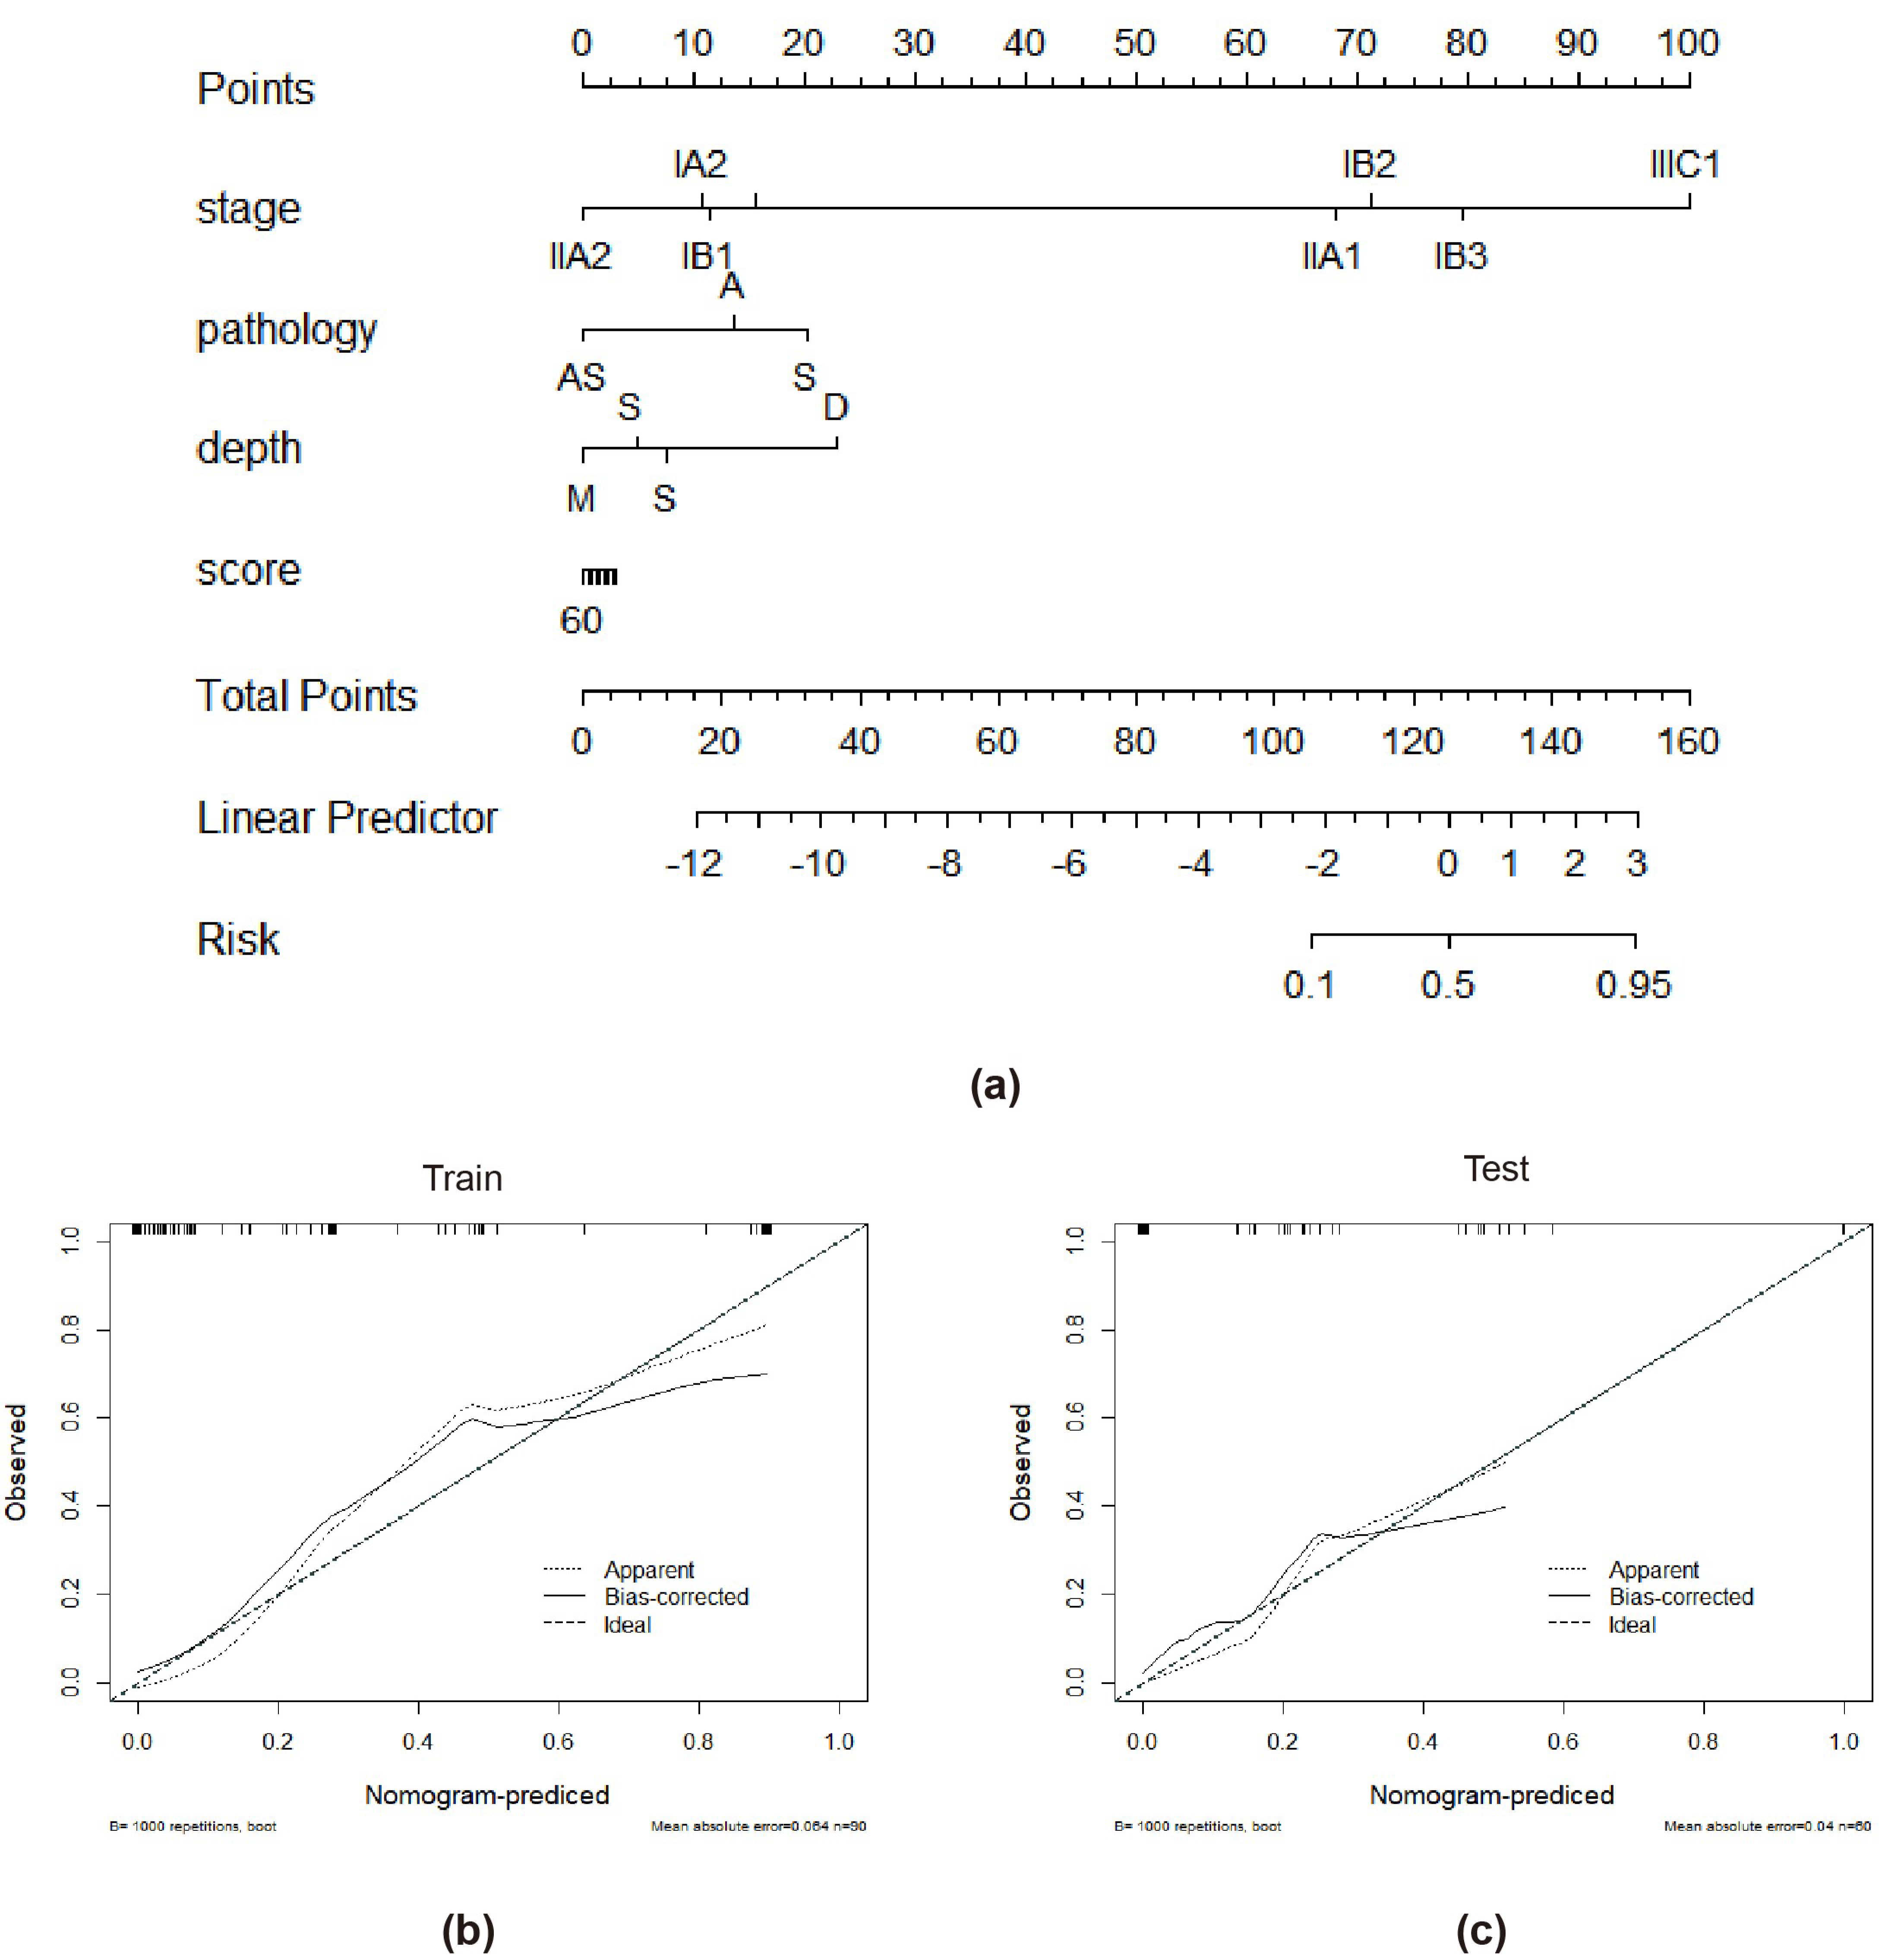

3.3. Performance of the Combined Model and the Radiomics Nomogram